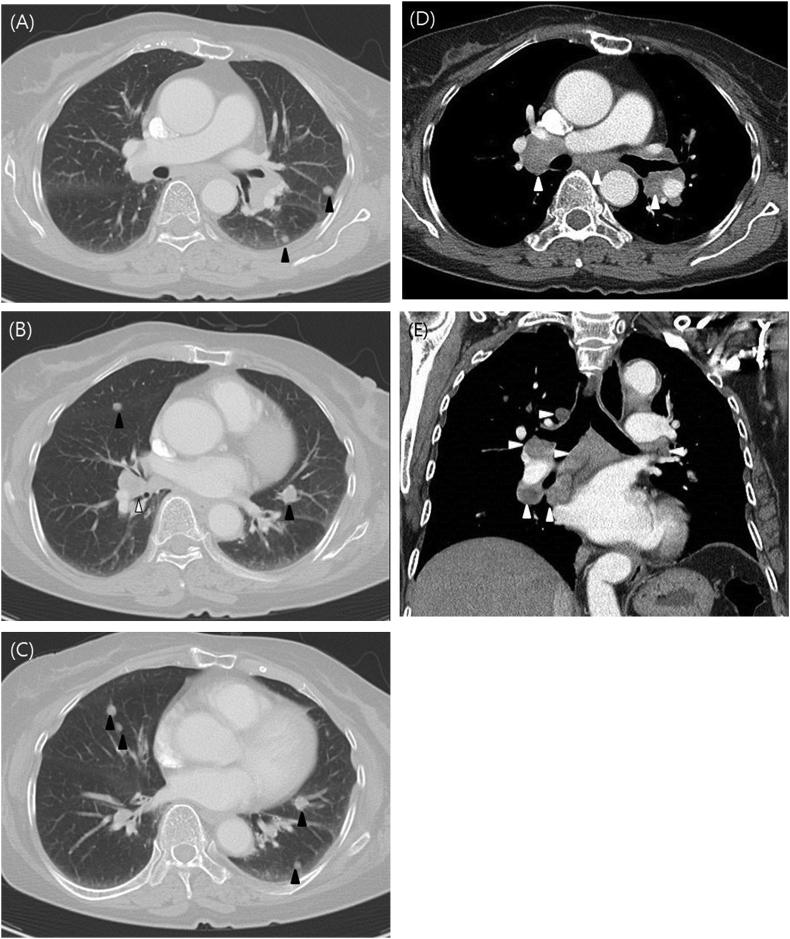

A 73-year-old female living in the rural area presented with chronic cough. She had multiple rounded nodules less than 1cm in size in both lungs, and bilateral mediastinal lymphadenopathy in chest images, which could be confused with metastatic cancer. Bronchoscopy did not show bronchial anthracofibrosis, and positron emission tomography (PET) scan showed F-18 fluorodeoxyglucose (F FDG) uptake. Surgical biopsy histology confirmed that the nodule was anthracofibrosis and the lymph node was reactive hyperplasia. Pulmonary function was accompanied by obstructive ventilatory defects, and clinical symptoms and lung function were improved after the use of inhaled corticosteroid and bronchodilator.

一名居住在农村地区的73岁女性因慢性咳嗽就诊。胸部影像显示双肺有多个直径小于1cm的圆形结节,双侧纵隔淋巴结肿大,可能会与转移性癌症混淆。支气管镜检查未显示支气管炭末纤维化,正电子发射断层扫描(PET)显示有F-18氟脱氧葡萄糖(FDG)摄取。手术活检组织学证实结节为炭末纤维化,淋巴结为反应性增生。肺功能伴有阻塞性通气功能障碍,使用吸入性糖皮质激素和支气管扩张剂后临床症状和肺功能得到改善。